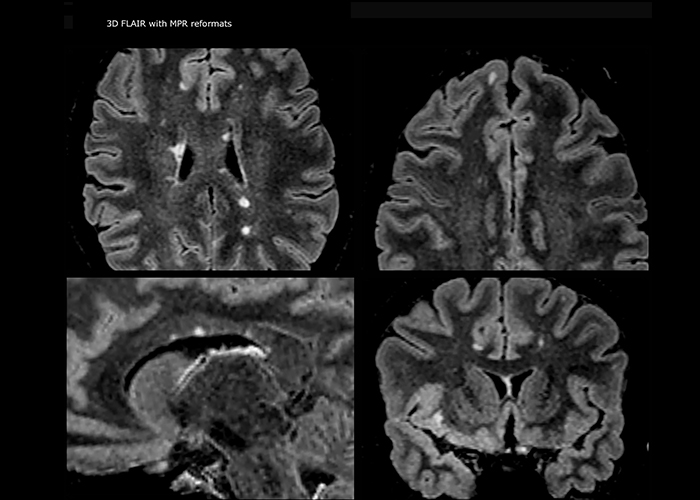

Imaging MS in brain

For MS imaging in the brain, Dr. Savatovsky uses 3D FLAIR as the basic sequence to visualize the lesions and assess the situation and lesion load. “We count the lesions in each location to determine if the criteria of the disease are fulfilled. We use a T2-weighted sequence because our neurologists are used to it. We compare the lesion load on FLAIR with a 3D T1 post-contrast sequence to help us determine whether lesions are old or new. We typically administer the contrast before the patient enters the machine because it shortens the examination time and allows to visualize active lesions that tend to be more visible after several minutes. When a differential diagnosis is difficult, we add sequences such as susceptibility imaging, because some focal MS lesions have a small vein in the center[3].”